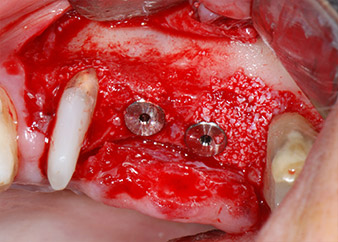

Fig. 2 et 3 : Après élévation des lambeaux, un mois après le retraitement endodontique et le démarrage du traitement parodontal global, la racine de la dent 24 présentait une perte totale d'os et d'attache.

Nous avons toutefois maintenu notre projet initial de conservation des deux dents comme piliers temporaires d'un bridge pendant la période de six mois nécessaire à l'ostéointégration des implants. À la prochaine incision, la situation devrait être réétudiée. Premièrement, afin de gérer le problème endoparodontal, la surface de racine restante a été soigneusement débridée à l'aide d'un équipement piézoélectrique (Piezomed, W&H, utilisé avec l'insert en forme de spatule S1, initialement conçu pour limer la paroi sinusienne latérale) (Fig. 4).

implants prêts à recevoir les vis de couverture

Fig. 12 : Les deux implants sont en place et prêts à recevoir les vis de couverture.